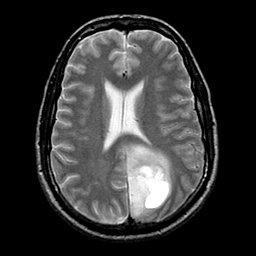

glioma overlay -- Slice #17

[Home][Help][Clinical] Slice 17